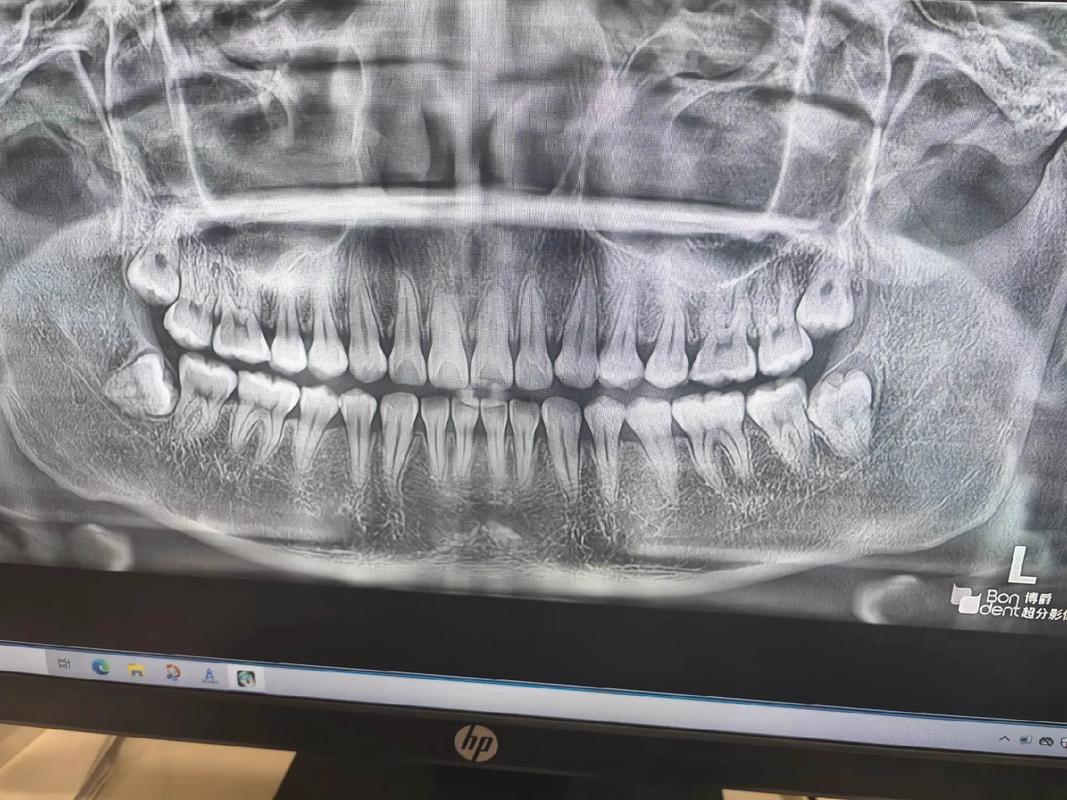

智齿是人类的第三磨牙,通常在17-25岁萌出,这一阶段被称为“智齿萌出期”,但并非所有人的智齿都会顺利萌出:部分人先天缺失智齿(上颌或下颌),部分人的智齿因颌骨空间不足而“阻生”(埋在牙槽骨内或牙龈下),无法正常长出,正畸前,医生通常会拍摄全景片(X光片)检查牙齿情况,若智齿完全埋伏在颌骨内且未对邻牙造成压迫,可能暂时无需处理,这也让患者误以为“自己没长智齿”。

第一步:拍片检查,建议拍摄全景片或CBCT(三维锥形束CT),明确智齿的位置(萌出/埋伏)、方向(正位/阻生)、与邻牙及下颌神经管的关系,判断是否存在上述风险。

| 为什么正畸前拍片没智齿? | 可能是拍片时智齿完全埋伏在颌骨内,且未开始萌出,X光片上显示为“牙胚”或未显现;也可能是正畸前检查时医生判断智齿暂无风险,未特别告知,建议正畸前和正畸后定期拍全景片,动态监测智齿状态。 |